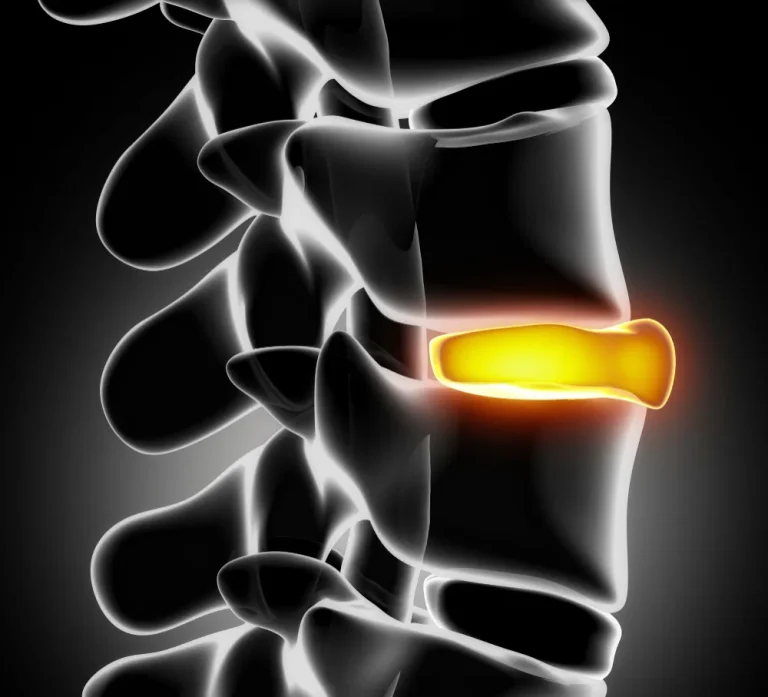

disc rupture

โรคหมอนรองกระดูกสันหลังปลิ้น

disc rupture spine

โรคหมอนรองกระดูกสันหลังเคลื่อน/ทับ เส้นประสาท